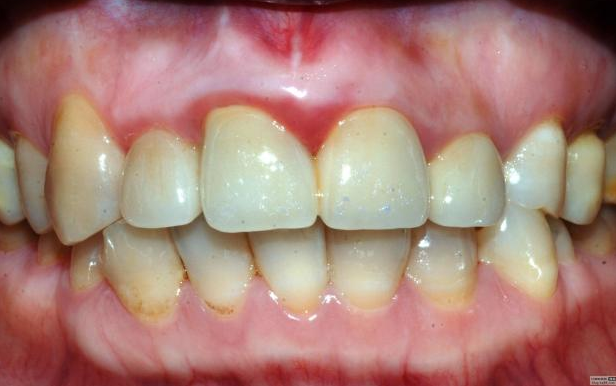

最近接到這樣一位患者,上前牙氧化鋯聯(lián)冠修復(fù)不足一年時(shí)間,現(xiàn)患者主訴左上前牙疼痛來診,檢查發(fā)現(xiàn)上前牙冷熱無反應(yīng),扣診(++),牙齦紅腫,探出血,冠邊緣不密合, X片示基牙全部已做根管治療,但是根管充填全部欠填。

先不評論修復(fù)體的顏色、形態(tài)、密合性及生物學(xué)寬度的問題,就患者而言對修復(fù)體還是比較滿意的,是因?yàn)樾迯?fù)后不久牙齒開始疼痛,吃了好多藥也不起作用才來就診檢查的,但患者剛開始不愿拆冠,經(jīng)過詳細(xì)的溝通后才同意拆冠——冠延長術(shù)——根管再治療——愈合——重新修復(fù)。可見患者雖然花了較高的費(fèi)用,但對我們醫(yī)生的要求還是很低的,但就是這么低的要求也不見得所有醫(yī)生能夠滿足患者。這個(gè)患者即使冠沒有問題,也得拆冠?;颊咭彩茄捞鄄艁碓\治的,在修復(fù)之前一定要做完善的根管治療。

病例1 由于根管充填不完善造成修復(fù)體拆除

修復(fù)后出現(xiàn)根尖周炎癥狀 根管再治療后病變愈合